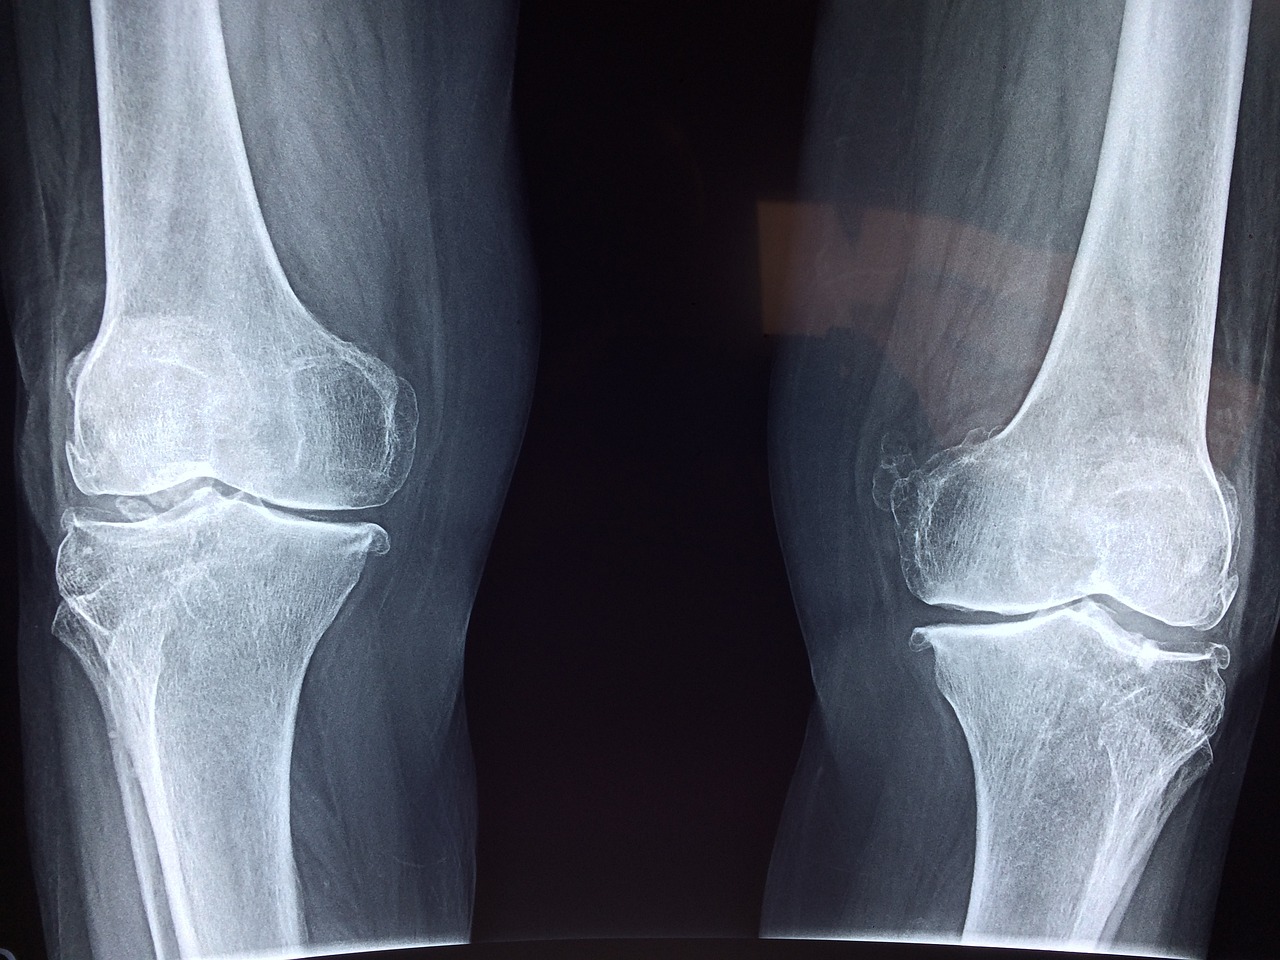

골관절염

골관절염은 나이가 들면서 연골이 닳아 없어지는 질환으로, 무릎 통증의 가장 흔한 원인 중 하나입니다. 연골이 닳아 없어지면 뼈가 직접 맞닿아 마찰을 일으켜 통증이 발생하며, 이로 인해 무릎의 움직임이 제한될 수 있습니다.

류마티스 관절염

류마티스 관절염은 면역 체계가 관절을 공격하여 염증을 일으키는 자가면역 질환입니다. 이 질환은 무릎 관절에도 영향을 미쳐 심한 통증과 변형을 초래할 수 있습니다.